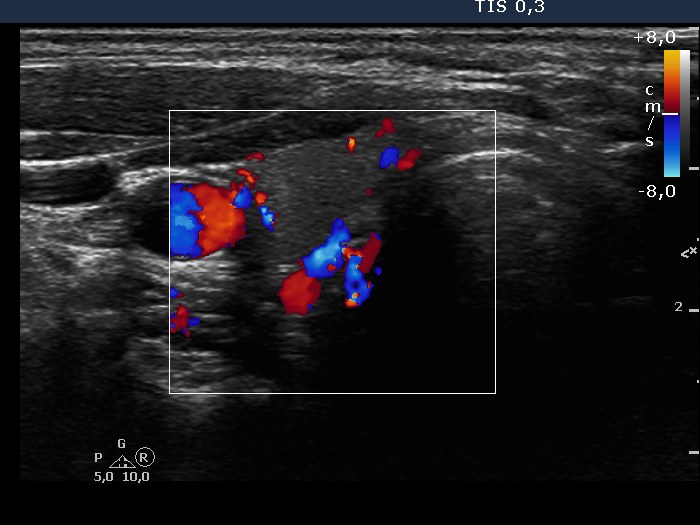

Ultrasonography: the thyroids were intact, i.e. the basic echo structure was echonormal and only a few small hypoechogenic areas were found. The echogenicity index was less than 1%. The vascularization was not specific.